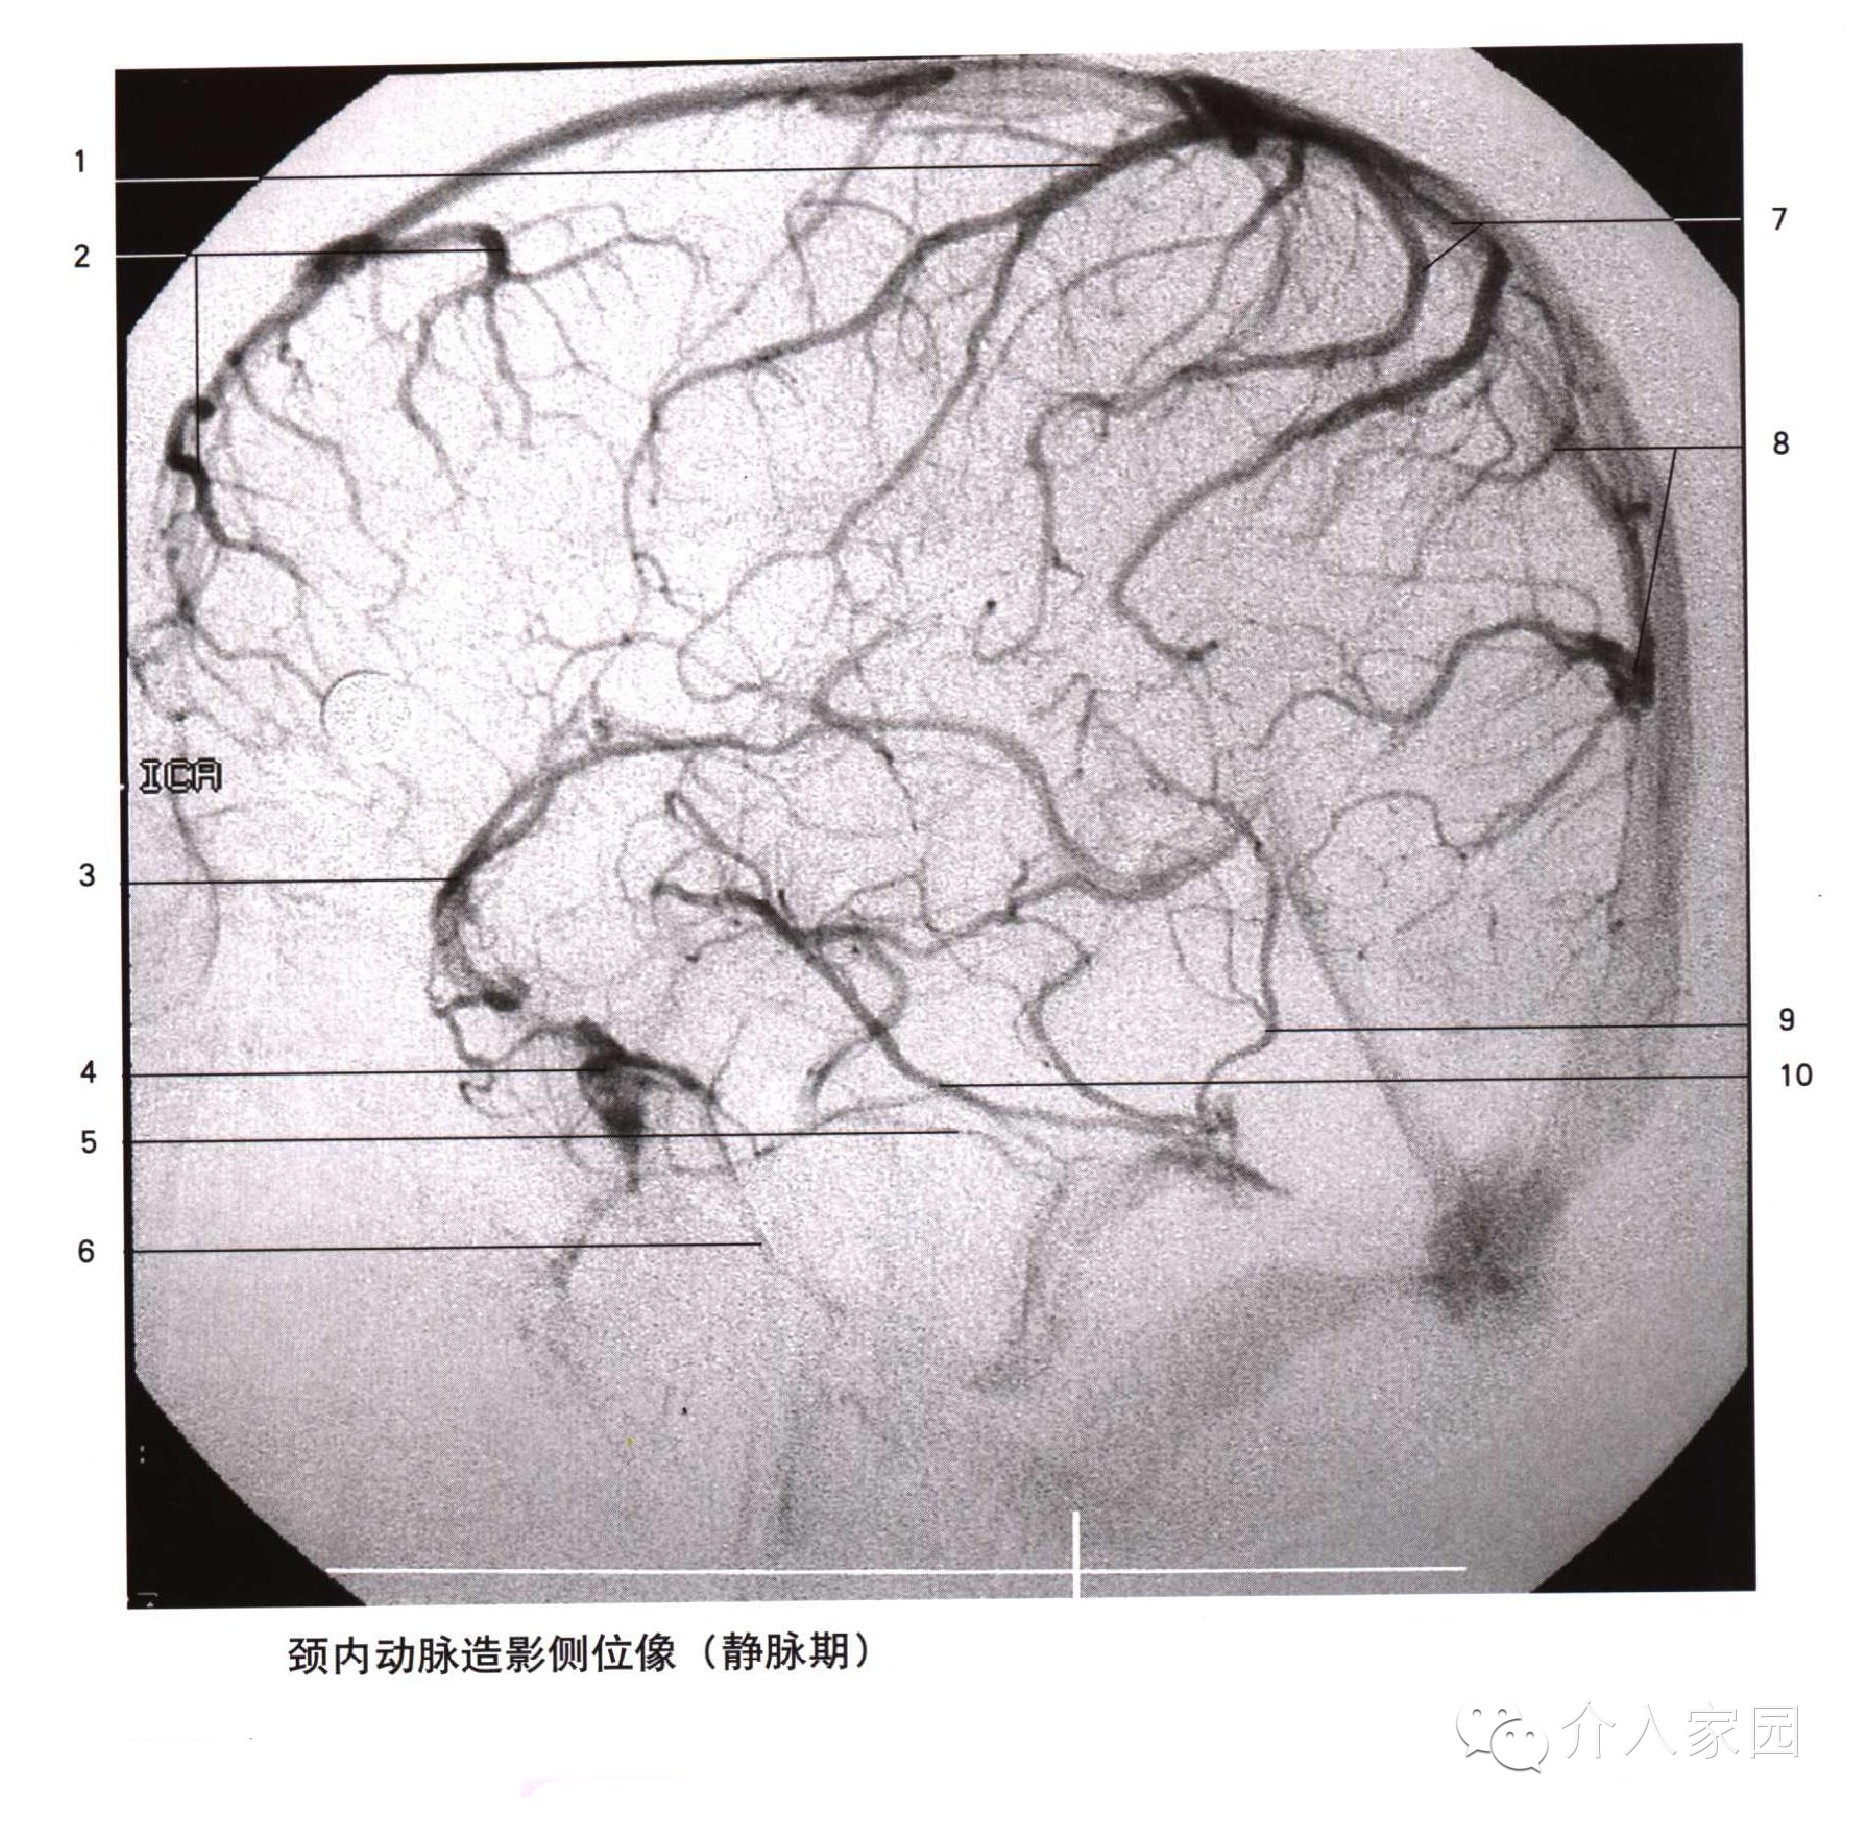

1、上矢狀竇 2、頂升靜脈 3、枕升靜脈 4、直竇 5、竇彙 6、橫竇 7、乙狀竇 8、中央溝靜脈 9、上吻合靜脈 10、額升靜脈

11、丘紋靜脈 12、靜脈角 13、大腦內靜脈 14、透明隔靜脈 15、基底靜脈 16、大腦中淺靜脈 17、海綿竇 18、岩下竇